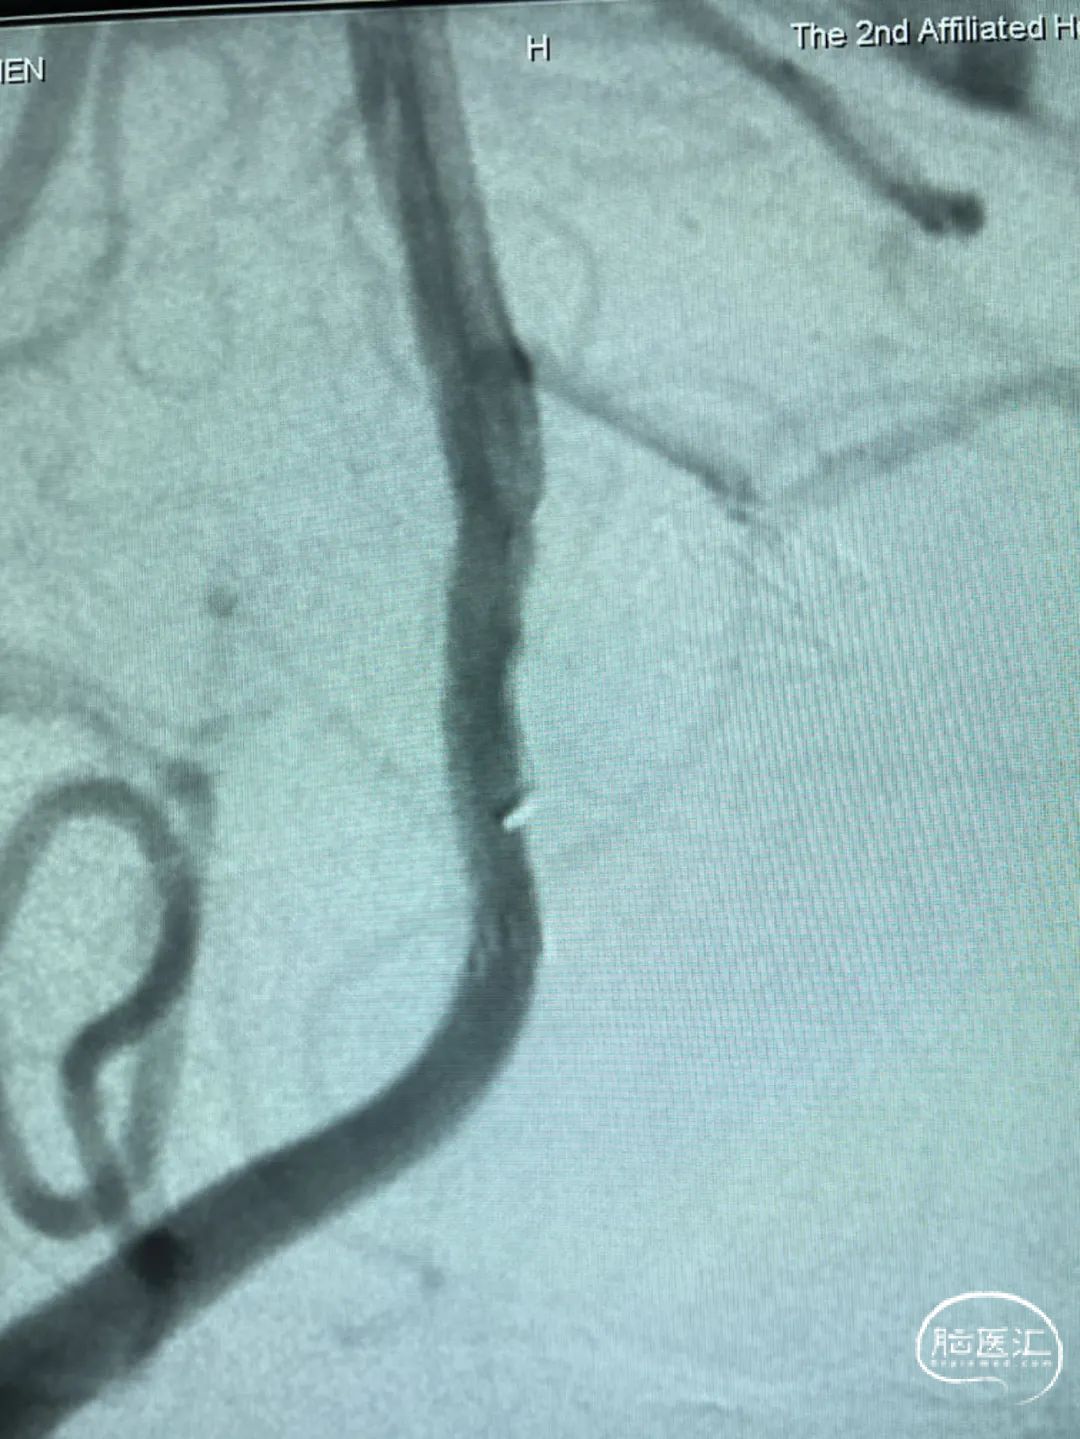

此为左侧大脑中动脉瘤,近端血管极为迂曲,瘤体有突出的子囊,动脉瘤与载瘤动脉有一定夹角,动脉瘤呈上窄下宽形状,M2段下干从瘤颈近端发出。

动脉瘤平均宽度5.41mm, 最小高度为3.71mm,瘤颈约为4.94mm,使用WEB™ SL 6*3mm瘤内扰流装置进行栓塞治疗。

释放WEB™:缓慢推出WEB™从种子至萌芽状态,继续向瘤腔内远端缓慢推送WEB™至萌芽至开花间状态;将WEB™和VIA™送至瘤顶,固定WEB™推送杆回撤VIA™,WEB™完全释放。

经造影可见WEB™尺寸合适,贴合瘤壁,覆盖瘤颈,且下支M2段分支及其他分支血管血流通畅。

解脱后,再次造影和Dyna-CT评估,可见动脉瘤瘤腔内有明显造影剂滞留,分支血管血流正常。